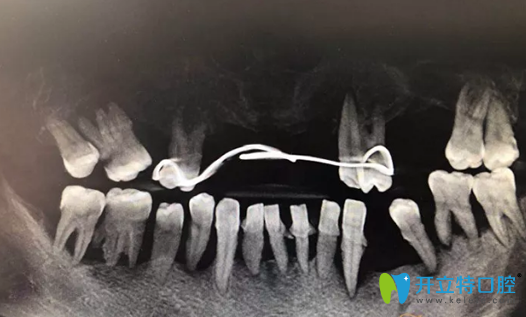

種植修復(fù)前CBCT影像:

重慶牙博士種植修復(fù)前CBCT影像

種植牙術(shù)后即刻照片及修復(fù)后CBCT影像:

重慶牙博士徐孟輝種植牙術(shù)后即刻照片及修復(fù)后CBCT影像